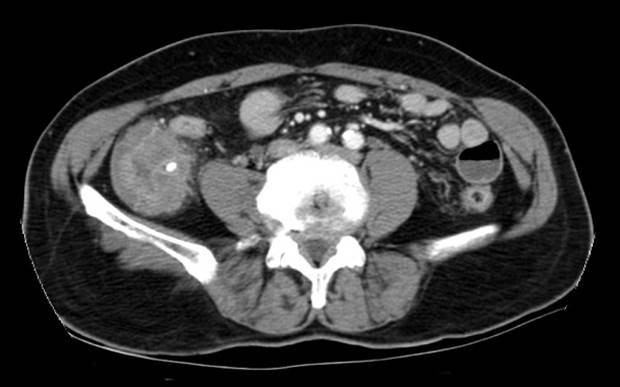

Appendicitis¿¡ ´ëÇÑ ³»½Ã°æ »çÁøÀ» º¸¿©µå¸°´Ù´Â °ÍÀº Âü ¼Û±¸½º·± ÀÏÀÔ´Ï´Ù. ÀÓ»ó»óÀ¸·Î ÀǽÉÇϰí ÃÊÀ½ÆÄ³ª CT·Î Áø´ÜÇÏ°í ¹Ù·Î ¼ö¼úÇÏ´Â ±×·± º´À̱⠶§¹®ÀÔ´Ï´Ù. ±×·¯³ª °£È¤ Áø´ÜÀÌ ¾î·Á¿ö ³»½Ã°æ±îÁö ÇÏ´Â ÀÏÀÌ ÀÖ½À´Ï´Ù.